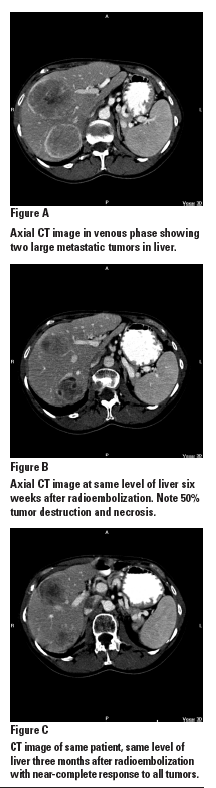

During the procedure, called selective internal radiation therapy (SIRT) or radioembolization, a targeted high dose of radiation is delivered to liver tumors. The treatment is performed as an outpatient procedure in radiology and requires the placement of a transfemoral microcatheter that is positioned in the hepatic artery. Using the liver’s unique vascular supply, millions of tiny microspheres charged with yttrium-90 are released into the hepatic artery in a carefully chosen location unique to that patient. The radioactive microspheres become implanted in the microvascular supply of the tumor, where they become permanently trapped. The microspheres emit beta radiation over a period of two weeks.

The targeted nature of SIRT allows us to deliver 40 times more radiation directly to tumors than is possible with conventional radiation, resulting in extremely high response rates with very few serious adverse events. This finding is particularly surprising given that the liver is one of the most radiation-sensitive organs in the body. But chemotherapy-insensitive, unresectable tumors are being completely destroyed with a single treatment. Microsphere therapy is succeeding where everything else has failed, especially when used early in the disease course. Microspheres have also been found to be more effective when given concurrently with state-of-the-art chemotherapy.

In our practice, we mostly use microspheres without concurrent chemotherapy, as a majority of patients are on a chemotherapy “break” to recover from some side effects, or their cancer is not responding to the current “best” chemotherapy. Many less common tumors that do spread to the liver are also being eradicated. This is rewarding, since we are able to provide patients with a better quality of life with fewer side effects while in treatment and extend their life expectancy despite a disease state for which no treatment was previously available.